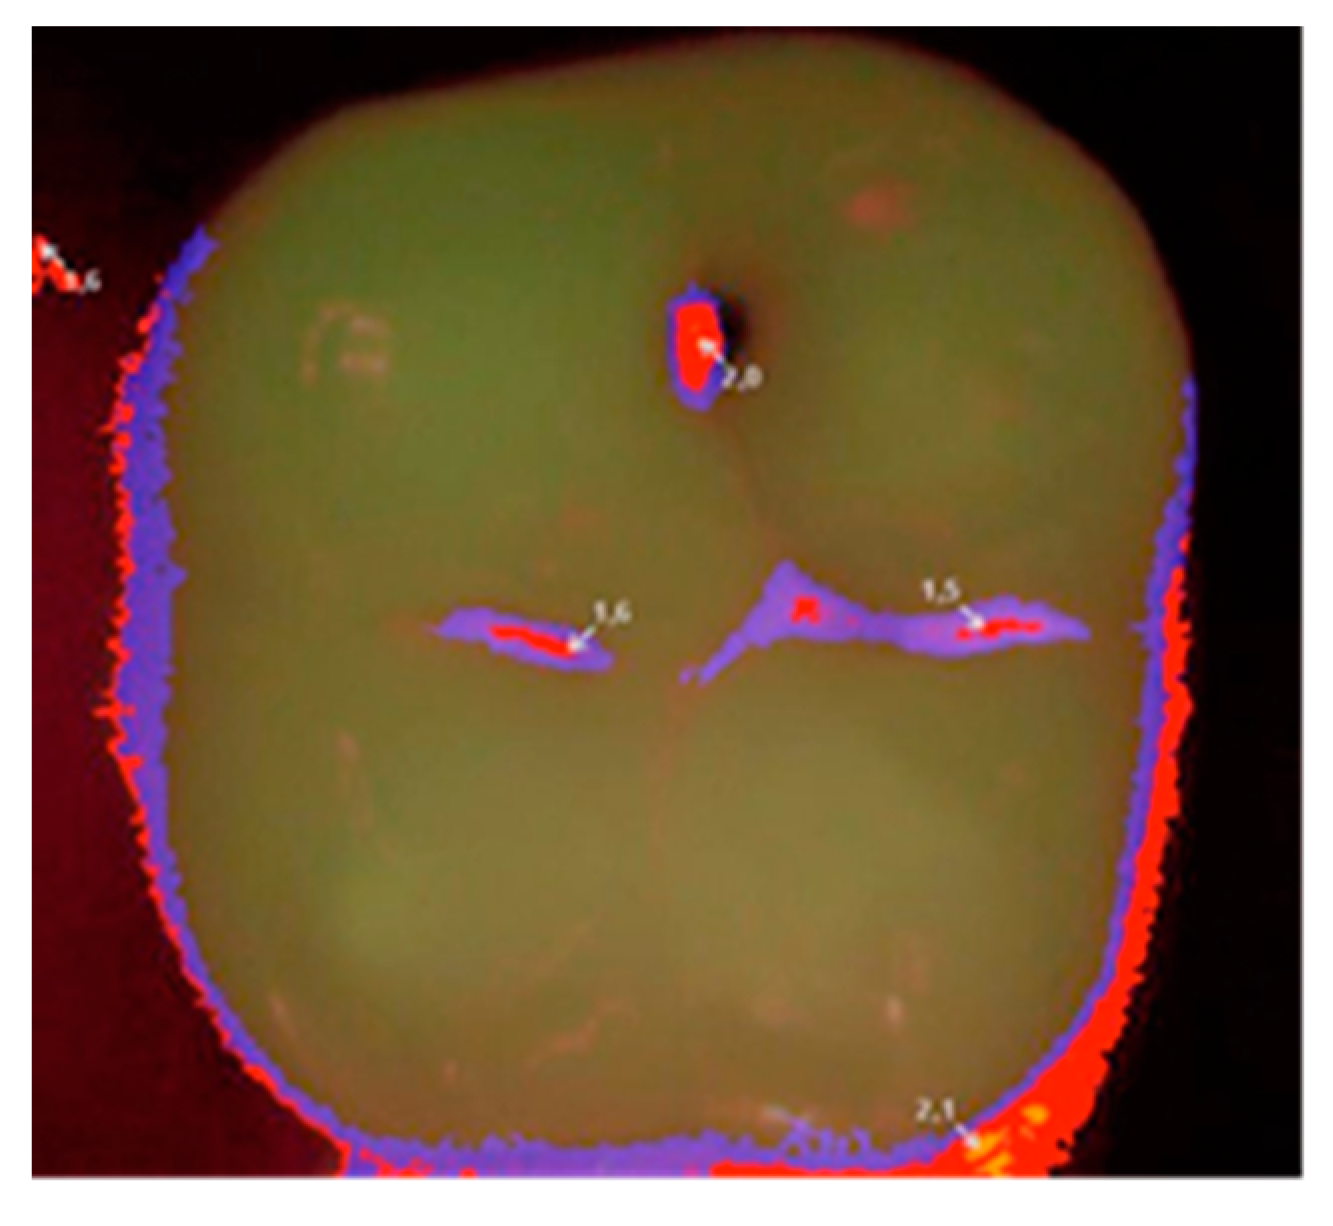

Each patient was qualified on the basis of a clinical statement that confirmed the presence of a small carious lesion, further validated by diagnostic results of Diagnodent (KaVo, Biberach, Germany) and a Vista Proof (Dürr Dental, Bietigheim-Bissingen, Germany) camera. An initial Vista Proof camera image (Figure 1) showing the extent and intensity of caries was recorded, and the corresponding numeric values (maximum) were saved.

Then, at appropriate time intervals (0, i.e., right after filling, and after 6, 12, and 24 months), the patients were subjected to clinical examination, and the fillings were evaluated according to the Ryge scale criteria [14] with the use of additional visual registration by means of a Vista Proof camera (Figure 2). During each follow-up visit, an intraoral photograph was taken for the record with a Canon EOS 30D digital camera with a Canon EF 100 mm f/2.8 L Macro IS USM lens and a Canon Macro Ring Lite MR-14EX. The photographs were taken before and after the cavities were prepared, as well as after filling each cavity with a given material (Figure 3). Control tests were complemented by a plaque/calculus evaluation using Greene and Vermilion’s oral hygiene index (OHI) index and Lange’s approximal plaque index (API) [18].

Figure 1. Image from a Vista Proof camera showing Tooth 47 qualified for treatment.